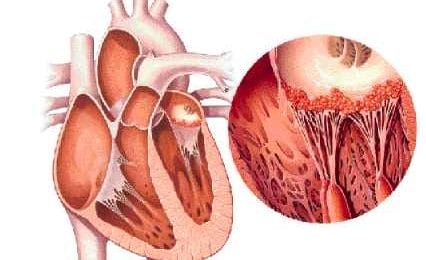

Pancarditis

Pancarditis is de algemene aanduiding voor ontstekingen...